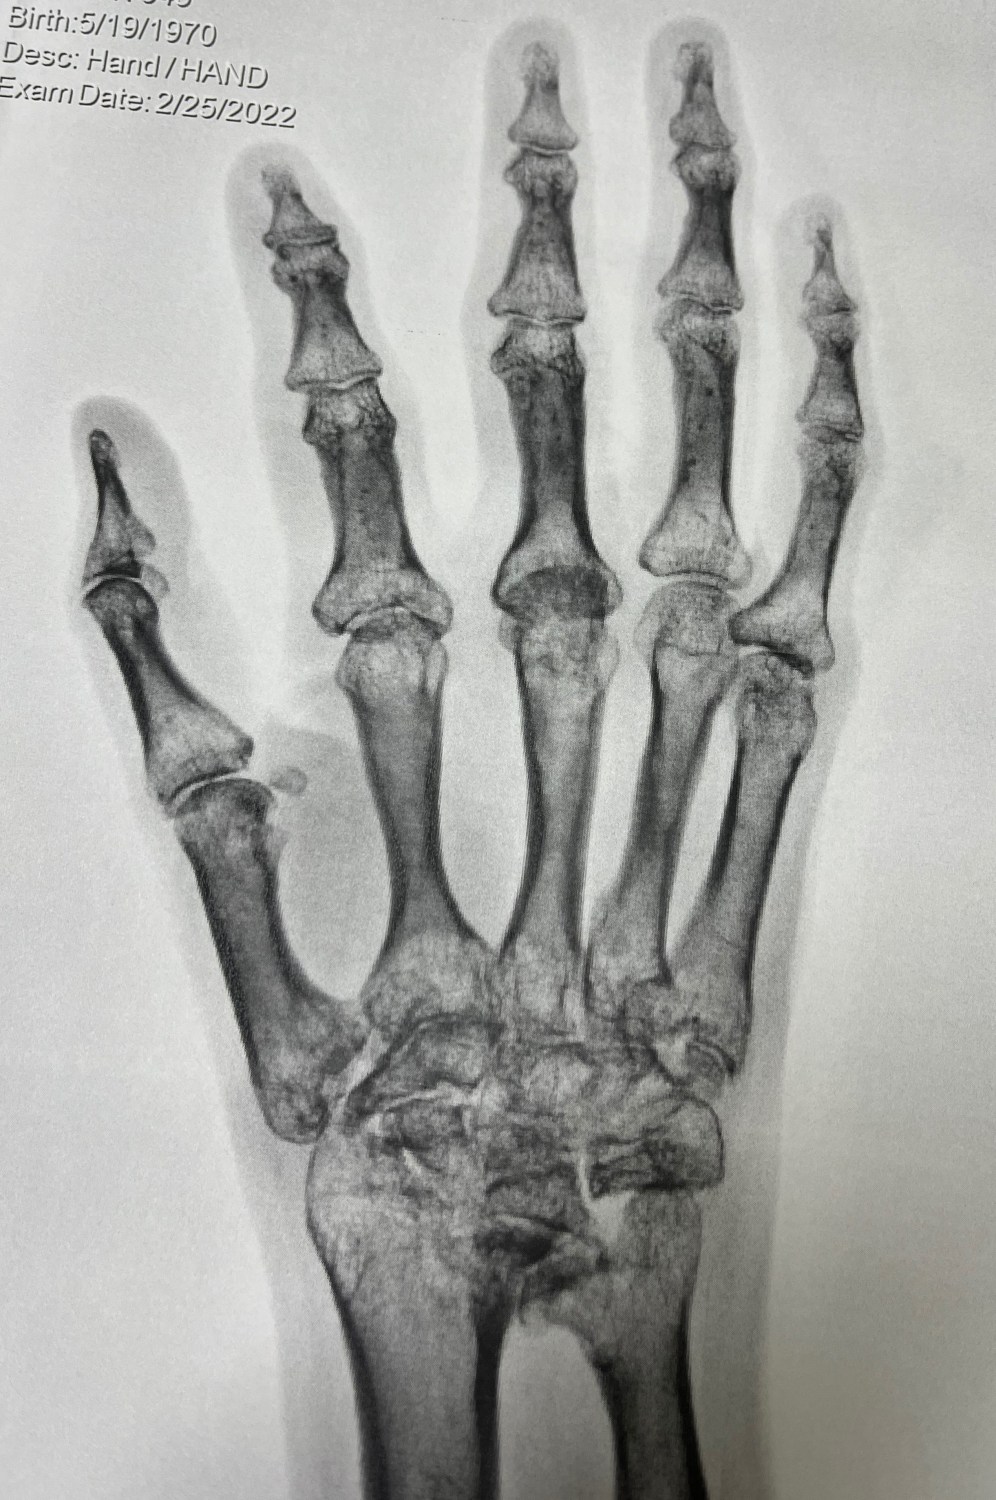

Also during this time I thought I would see if there was anything available to help my right hand. My rheumatologist has consistently said there’s not much they can do for it surgically, however, we agreed that occupational therapy might we worth a try. While Physical Therapy works on gross motor skills; Occupational Therapy works with the smaller muscles, for fine motor skills. I only went for a few times, as it soon became apparent there was not much they could do either. So, I guess I am stuck (literally) with this hand.

As you can see, there is very little joint space anywhere and my wrist just looks like one giant fused ball of bone. You can understand why fine motor skills have become increasingly difficult.